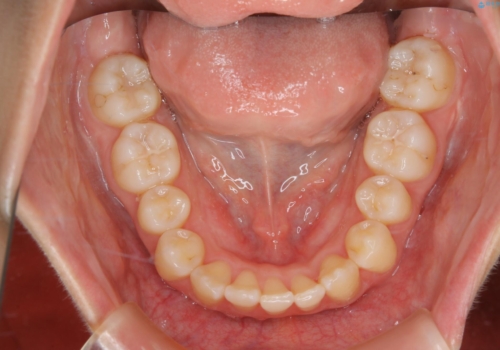

下顎前歯の先天欠損と上顎前歯のクロスバイト:インビザライン治療

元々下の前歯が1本欠損しており、上下の噛み合わせや、歯のサイズバランスを考慮しながら治療を行いました。

下顎切歯が1本欠損しているため、上顎前歯部を少しずつストリッピングして、上下の噛み合わせ、バランスの向上を図りました。